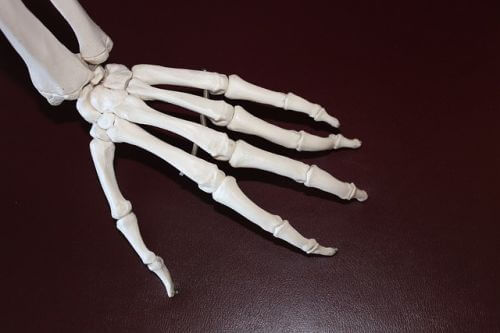

류마티스 관절염의 증상은 먼저 손에서 나타납니다. 손가락손허리뼈와 몸 쪽손가락관절에 침범하지만, 질병 후기에는 먼쪽 손가락관절에도 침범될 수 있습니다. 류마티스관절염이 진행되면서, 손이 변형이 일어나서 손가락손허리뼈는 척골편위가 발생하고, 백조목 변형 및 단추구멍 변형이 나타날 수 있다. 또한, 건초염 혹은 건막의 결절에 의한 방아쇠 손가락이 유발될 수 있고, 심한 경우 건파열이 생기며 4.5번째 수지의 신전부에서 가장 호발합니다. 류마티스관절염의 팔꿈치관절의 활막염은 류마티스환자의 50%에서 관찰된다. 팔꿈치에서의 구축도 잘 오지만, 환자는 잘 모를 수 있으니 주의가 필요합니다.